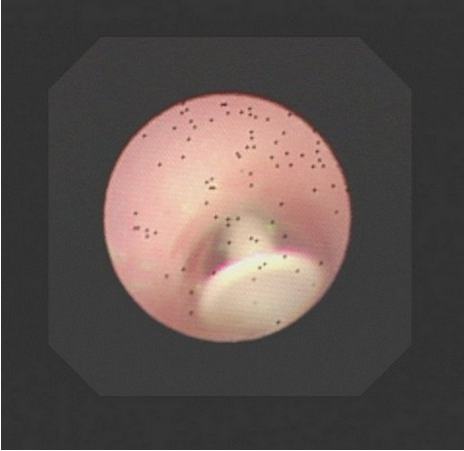

左圖:醫療團隊透過支氣管鏡檢查,看到異物塞在左支氣管開口處。

中圖:團隊進一步做電腦斷層排查原因,發現是卡在左支氣管入口的異物使氧氣無法進入左肺部。

右圖:卡進孩子支氣管的硬式隱形眼鏡吸棒,上面依稀可看見咬痕。